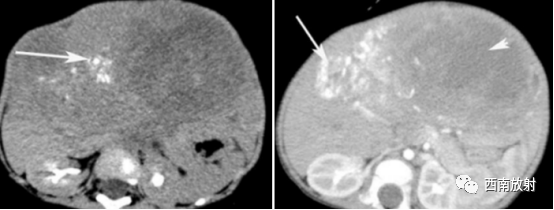

▲病例1:肝母细胞瘤:CT平扫显示肝左叶S2/3类圆形稍低密度肿块,边界模糊,增强扫描动脉期病灶显示不均匀强化、以边缘强化为主并见增粗的肝左动脉供血,门脉期及延迟期病灶强化逐渐减退。(病例来源:李钱程.儿童肝母细胞瘤的 CT诊断中表现及误诊分析[J].中国CT和MRI杂志,2020.18(11):107-109.)

▲病例2:肝母细胞瘤。图1:CT平扫肝左右叶肿块,呈低密度,内部密度不均。图2肝内可见钙化灶。图3增强扫描肝内病灶不均匀明显强化,片状或结节状强化,见假包膜结构,图4可见肝内转移灶。

▲病例4:胎儿型肝母细胞瘤:男,9个月,肝右叶肝母细胞瘤,CT增强扫描示肿 瘤与周围正常肝组织边界清楚,似有假包膜 (短箭头),其内有裂隙状低密度区,瘤内可见较多粗细不一的肿瘤血管 (长箭头),下腔静脉主要为受压改变 (箭头 )。病理为肝母细胞瘤,胎儿型。

▲病例5:男,6个月,肝母细胞瘤,CT增强扫描示瘤区强化密度稍低于正常肝组织,肿瘤呈不均匀性分隔样明显强化,结节状稍高密度区明显强化(箭头 ),坏死或液化区无明显强化,瘤内可见条状钙化影(长箭头),瘤周血管受压(短箭头 )。病理为肝母细胞瘤,混合型。

▲病例6:男,1岁,肝左右叶肝母细胞瘤,化疗前CT平扫肝内见一巨大稍低密度肿块影,密度不均匀,内见不规则斑片状更低密度影及沙粒 状钙化灶分布(长箭头 ),病灶边界模糊。穿刺活检为混合型肝母细胞瘤。化疗后,肿瘤 体 积 明 显 缩小(短箭头),其内钙化增多(长箭头 )。